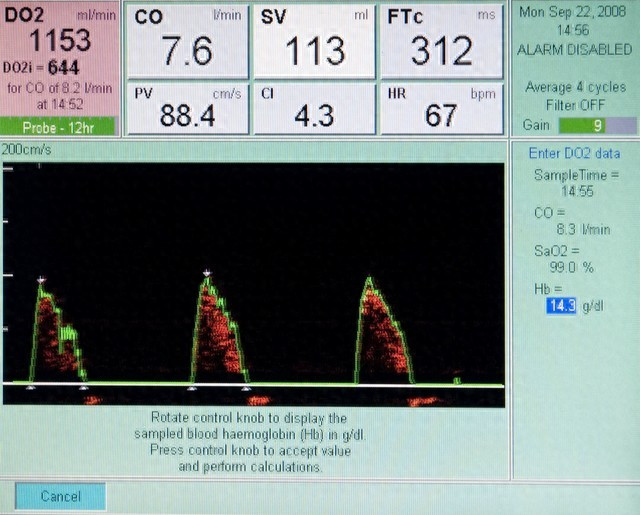

第一个检查:心脏超声

低压,医学上叫舒张压,它反映的是心脏舒张时,血管里的最低压力。低压高,很多时候和心脏功能、血管弹性脱不了干系。

比如有些患者,因为长期熬夜、压力大、爱生气,导致心率偏快,心脏舒张的时间变短,血管里的血液来不及回流,压力自然就降不下来;还有些人是因为心肌肥厚,心脏泵血的 “泵体” 出了问题,也会让低压居高不下。

做心脏超声,能清楚看到心肌的厚度、心室的大小、心脏的收缩和舒张功能,还能排查有没有心室肥厚、瓣膜反流这些问题。早发现,就能早干预,避免小问题拖成心肌缺血、心衰的大麻烦。

我之前有个 40 岁的患者,低压常年 95 左右,总说胸口发闷,一开始没当回事,后来做心脏超声发现心肌已经轻度肥厚了。赶紧调整生活方式,配合中药调理,半年后低压降到 85,复查心脏超声,心肌厚度也恢复了正常。